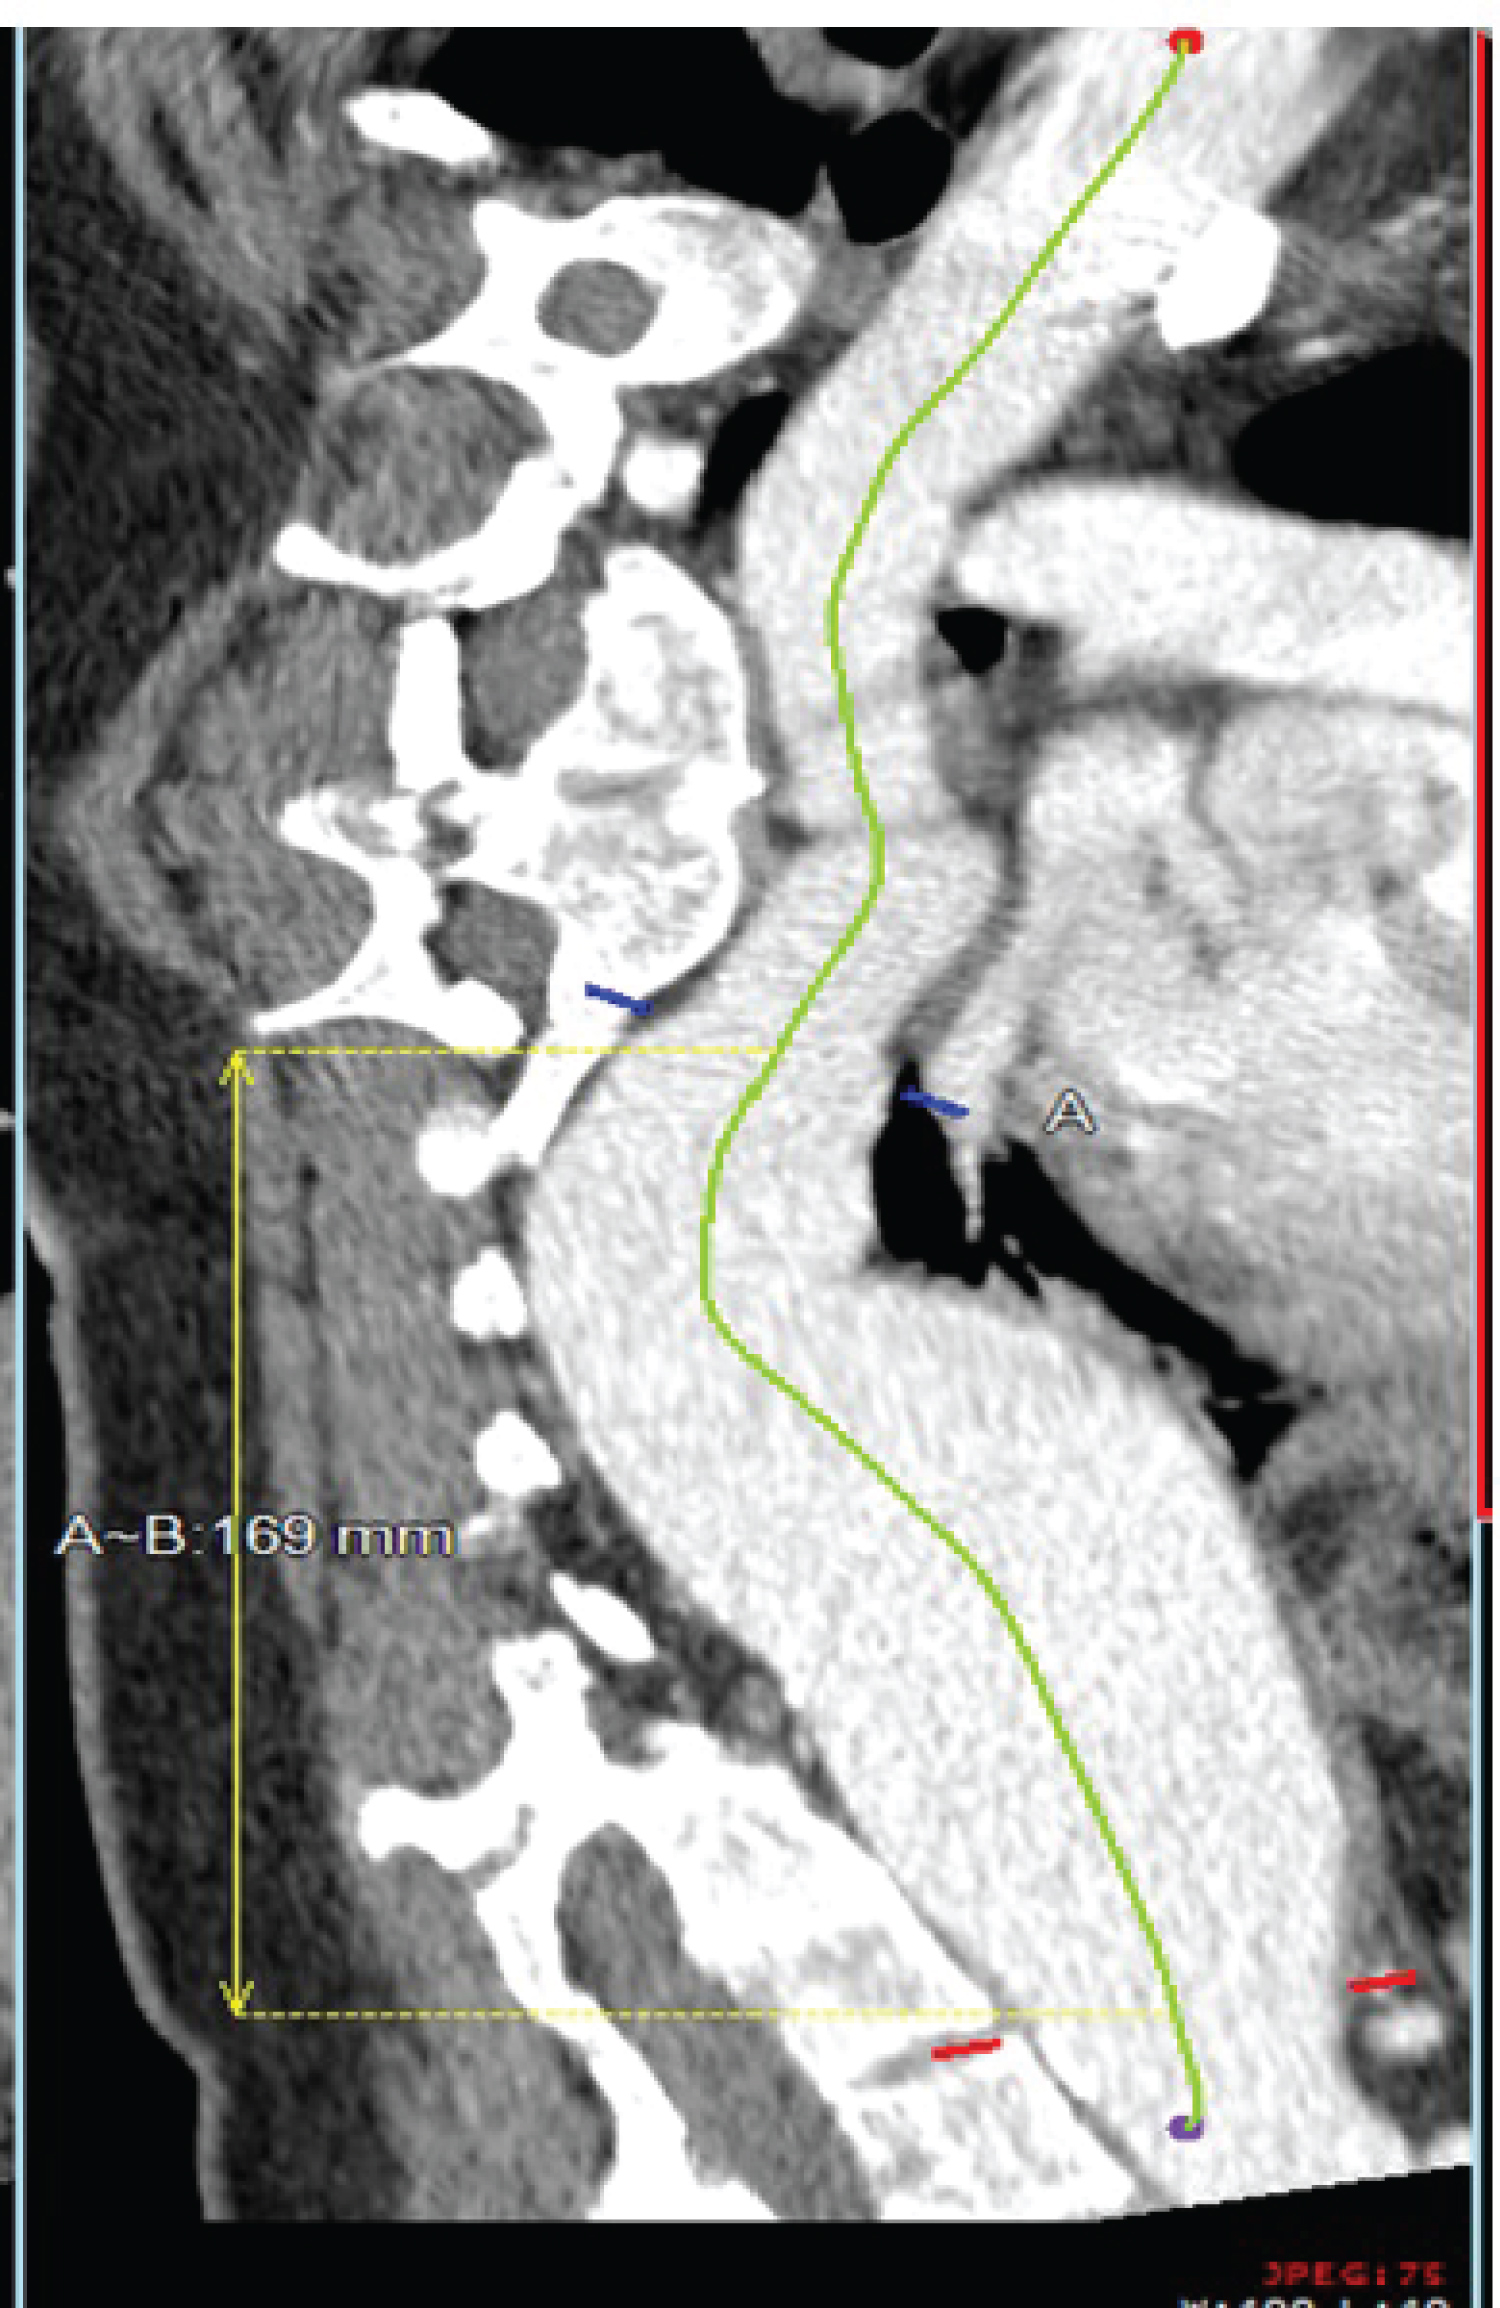

A 36-year-old woman with no significant past medical history presented to the emergency department with worsening suprapubic pain that had been present for 4-5 months and was found to have a urinary tract infection and symptomatic endometriosis. In the emergency department, computed tomography (CT) showed an incidental 7.3-cm descending thoracic aortic aneurysm. On presentation, the patient was hemodynamically stable with a heart rate of 116 bpm. She said that this could be normal during times of anxiety. On physical examination, she was noted to have normal pulses, well-perfused limbs, and to have moved all extremities appropriately, signaling no neurologic deficit at that time. She lacked any signs of marfanoid habitus. Laboratory results were notable only for hypokalemia, with a value of 2.9 mEq/L. She underwent a CTA confirming the diagnosis of a tortuous descending thoracic aortic aneurysm located at the distal thoracic component with aneurysmal dilation of 6.3 × 5.6 cm with no evidence of dissection or rupture (Figure 1). It is important to note the patient denied any family history of Marfan Syndrome and denied a family history of aneurysms. She also did not have any atherosclerotic risk factors, such as hypertension, hyperlipidemia, or diabetes mellitus, and was a lifetime nonsmoker. Upon genetic counseling, she was not found to have any known genetic associations with aortic aneurysms, including Marfan syndrome and Ehlers-Danlos syndrome.

Figure 1: CT of the chest confirmed a greater than 6 cm thoracic aneurysm extending from the mid-descending thoracic aorta to the arch of the celiac artery. View Figure 1